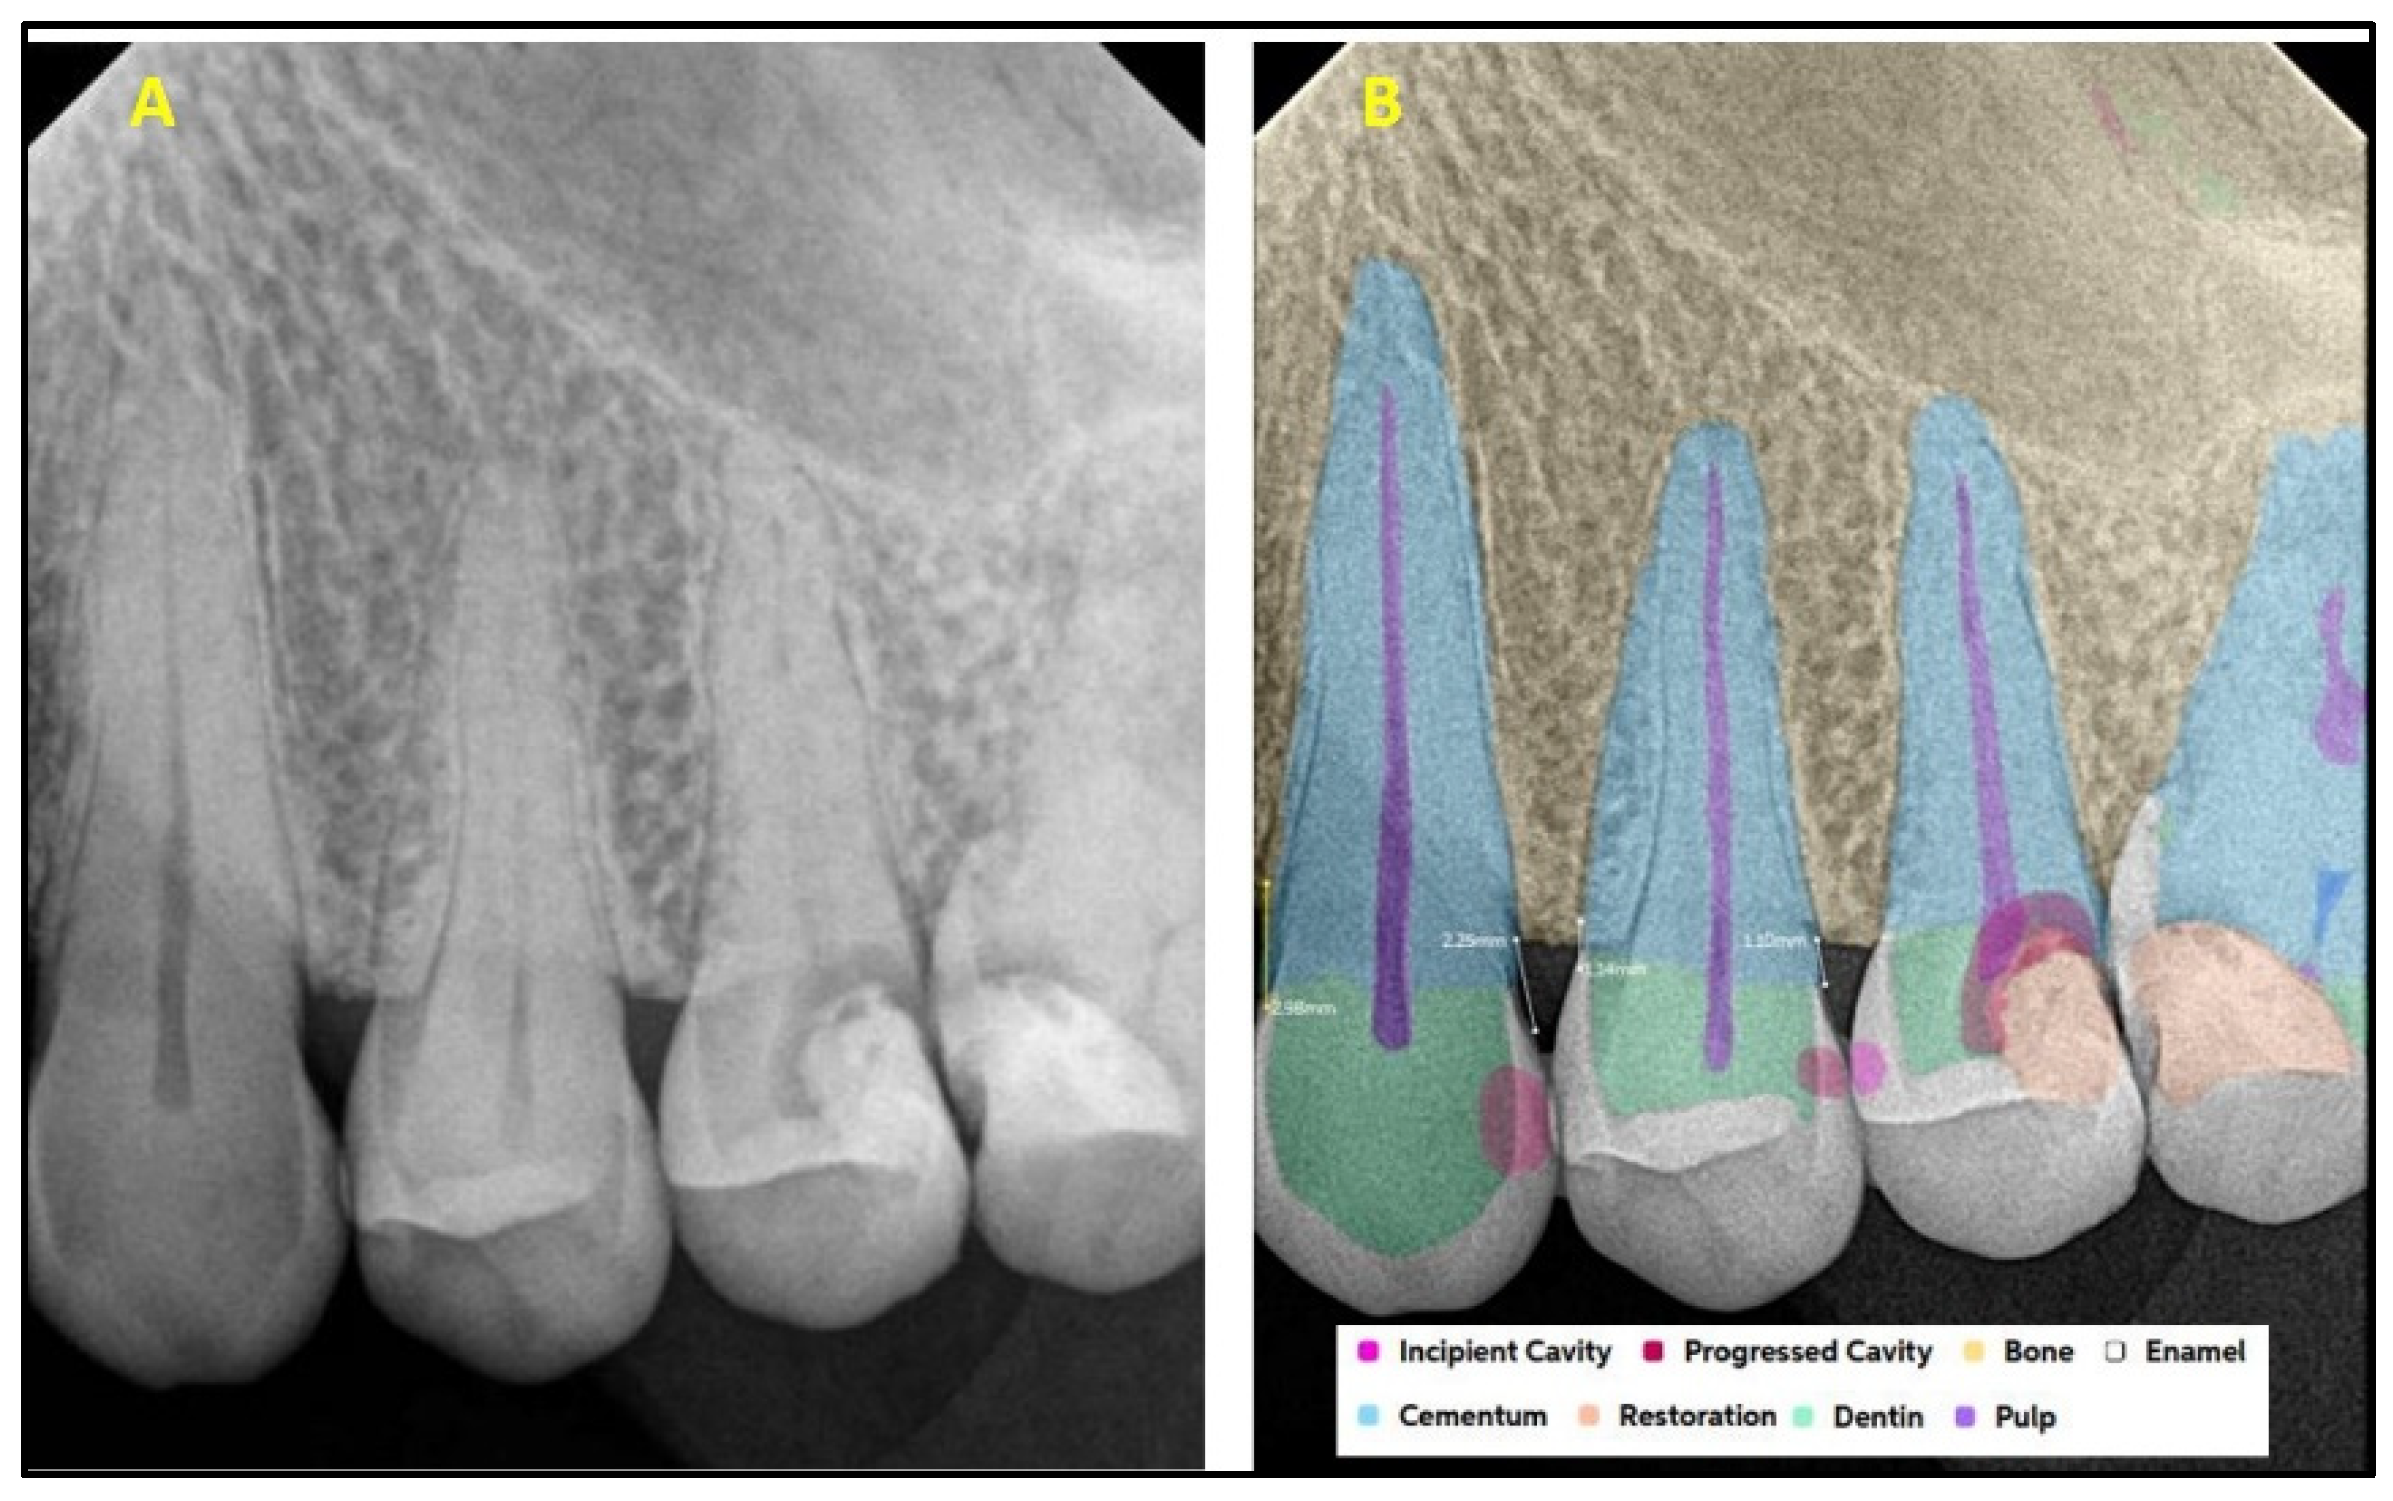

2.2. AI Software Architecture